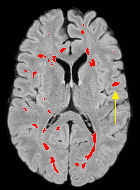

Patch size is another important parameter of the network. In computer vision applications such as object detection, usually a whole 2D image is used as a feature. However, full 3D medical images can not typically be used because of memory limitations. Fig. 4 shows examples of lesion memberships obtained with different sized 2D patches. As the patch sizes increases, the false positives that are mostly observed in the cortex tend to decrease. Fig. 5 shows a plot of Dice and LFPR with various patch sizes, ordered from left to right according to their increasing size. Note that smaller patches ( to ) produced significantly lower Dice and higher LFPR compared to other patches (), as seen from the memberships in Fig. 4. Also some of the highest Dice and lowest LFPR were observed for patches with large in-plane size, i.e., , , and . It was observed in Fig. 5 that there is no significant difference between Dice coefficients for , , or , but LFPR of both and are significantly lower than that of (). We chose as the optimal patch size. Other choices of smaller and patches (not shown) yielded worse results. Note that although training was performed with different patch sizes, the memberships were generated slice by slice, as the trained model consisted only of convolutions and did not need any information about patch sizes.

For this dataset, the training was performed separately with two sets of masks from the two raters of ISBI-21 data. Then two memberships were generated for each of the images. For each image, the two memberships were averaged and thresholded to form the final segmentation. Fig. 6 shows MR images and segmentations of subjects from the MS-100 dataset, where the subjects have high (cc), moderate (cc), and low (cc) lesion loads. For the subject with high lesion loads (#1), all methods performed comparably, although OASIS and LST underestimated some small and subtle lesions (yellow arrow). For the subject with moderate lesion load (#2), OASIS and S3DL underestimated some lesions (orange arrow) and LesionTOADS overestimated some (green arrow). When the lesion load is small and the FLAIR image has some artifacts (subject #3), LesionTOADS, S3DL, and OASIS produce a false positive (yellow arrow) in the cortex. LST shows underestimation, but FLEXCONN does not produce the false positive. The reason is partly because of the use of large patches, which can successfully distinguish between bright voxels in cortex and peri-ventricular regions.